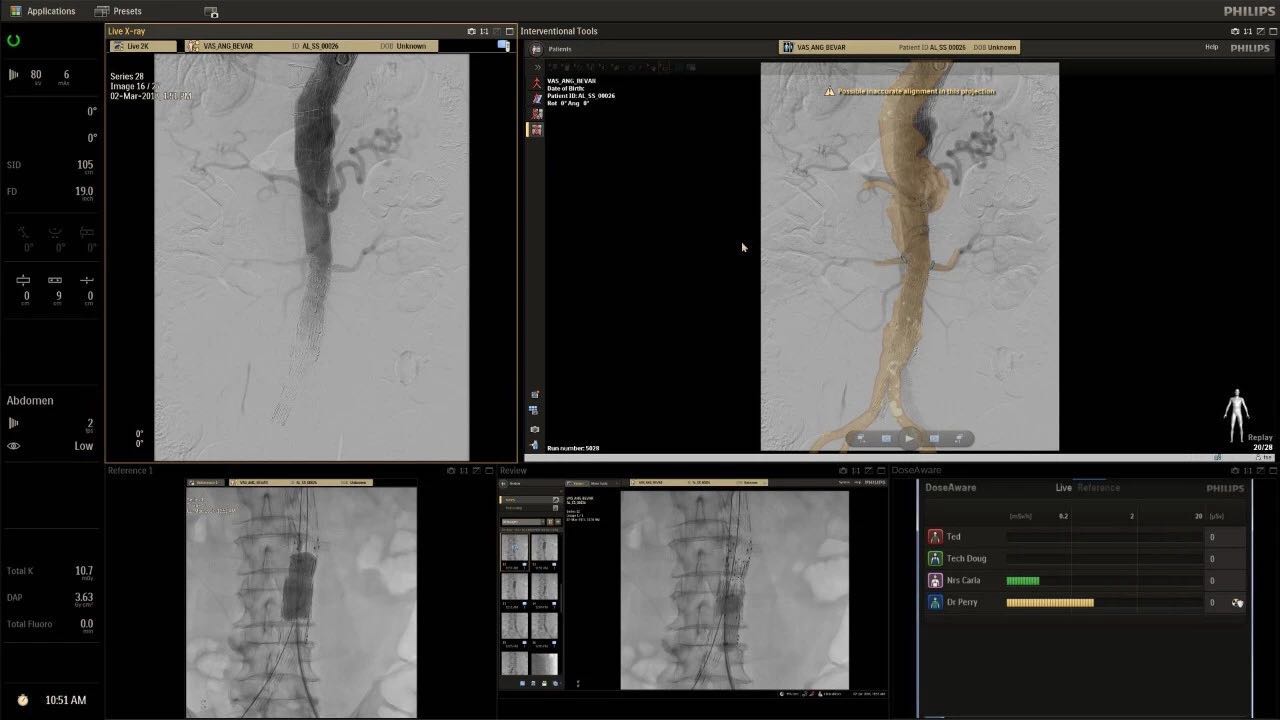

在日益復(fù)雜的干預(yù)期間,臨床醫(yī)生需要快速、輕松地可視化關(guān)鍵解剖結(jié)構(gòu)并確定手術(shù)過程中患者的變化。2019年1月17日,飛利浦宣布推出采用FlexArm的Azurion 7 C20,旨在提高圖像引導(dǎo)程序的定位靈活性。

帶有FlexArm的Azurion 7 C20 包含一系列創(chuàng)新技術(shù),使臨床醫(yī)生可以更輕松地在整個患者身上進(jìn)行二維和三維成像。當(dāng)臨床醫(yī)生移動系統(tǒng)時,圖像光束自動保持與患者的對準(zhǔn),允許更一致的可視化并使他們能夠?qū)⒆⒁饬性谥委熒稀?/span>

飛利浦表示,采用FlexArm設(shè)計的Azurion 7 C20可提供卓越的靈活性和直觀的控制。該系統(tǒng)由智能運動引擎驅(qū)動,可在八個不同的軸上移動,所有這些軸均由其單個“Axsys”控制器控制。臨床醫(yī)生的模擬測試表明,該系統(tǒng)有可能顯著減少患者,工作人員和設(shè)備的重新定位,從而改善微創(chuàng)手術(shù)的可及性,包括通過患者手腕進(jìn)入身體的手術(shù)(橈動脈入路),并降低患者的風(fēng)險。無意中拔出電線和管子,以及節(jié)省大量時間。該系統(tǒng)非常適合混合手術(shù)室(OR),可滿足一個房間內(nèi)的多種專業(yè)需求,例如手術(shù)和血管內(nèi)手術(shù)的組合。

FlexArm在不少于8軸的情況下旋轉(zhuǎn),從而創(chuàng)建幾乎無限的靈活性來執(zhí)行成像,從頭部到腳部在左側(cè)和右側(cè)進(jìn)行2D和3D可視化。圖像光束保持與患者對齊,允許在旋轉(zhuǎn)或角度期間更好地可視化解剖結(jié)構(gòu)。使用Axsys運動控制系統(tǒng)輕松操作支架。